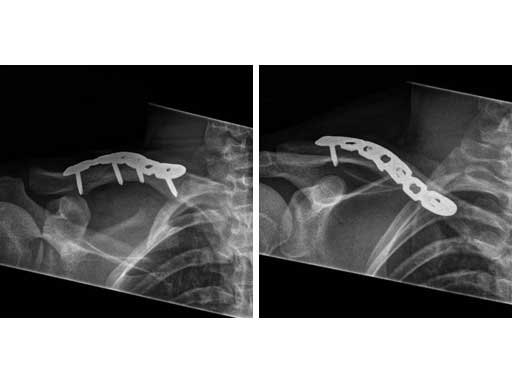

Fig 3ab Immediate postoperative x-rays.